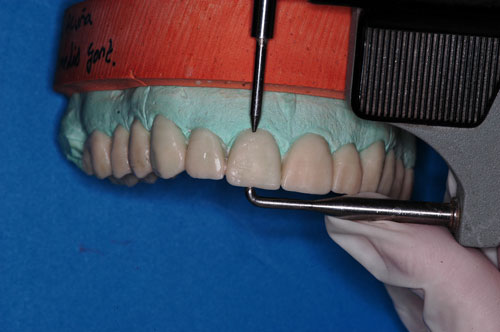

ENSAYOS DE TRATAMIENTO EN EL ARTICULADOR

y comenzamos a reducir la dimensión vertical en el sector anterior.

cada vez más… hasta lograr reducir 4 mm en los anteriores

logrado lo cual….

nos permitirá comenzar a reducir la altura de los posteriores hasta alcanzar el contacto anterior.

…y posterior

Con contacto de los últimos molares antagonistas derechos

y así obtener…la DV aproximada que el paciente tenía antes de que lo intervinieran (siempre hablando de “aproximaciones”…ya que la DV., así como la OH…cuando se pierden ..nunca se recuperan)

Sabemos entonces que en el articulador, la DV obtenida es por lo menos similar a la original del paciente y , en estas condiciones se tallan periféricamente las piezas dentarias en los modelos, pero en menor medida de lo que luego tallaremos en boca ( para tener un espacio interior de las futuras provisorias, y lograr un rebasado adecuado) y se comienza a costruir la G.A. en cera, utilizando la universal Ley de las Proporciones.

teniendo siempre en cuenta la proporcionalidad en base a cuidadosas mediciones de los parámetros anatómicos.